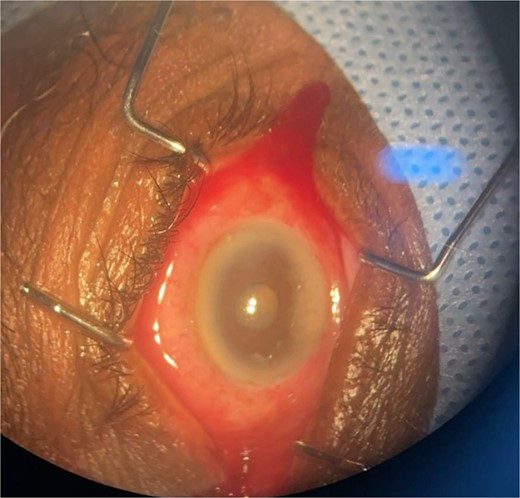

Patient 4: A 74-year-old Sudanese male visited the emergency room with severe left eye pain and loss of vision. His visual acuity was PL; examination showed hypopyon (Fig. 7). B-scan demonstrated vitritis (Fig. 8). He underwent emergency vitreous tap and intravitreal antibiotic therapy.

Surgical microscope examination showing hypopyon, chemosis, ciliary, and conjunctival injection in patient 4.